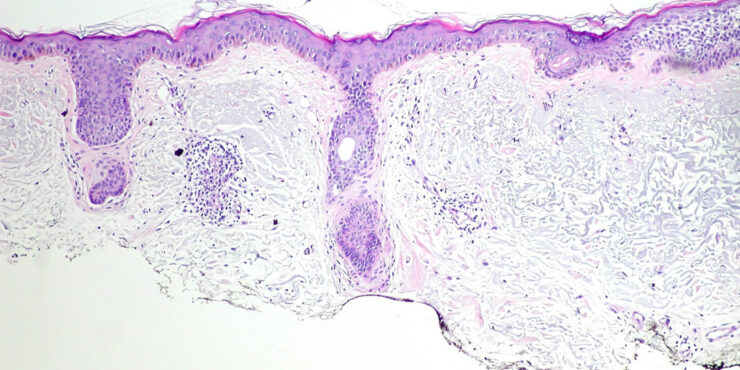

Bacillary angiomatosis = الورام الوعائي العصوي BACILLARY ANGIOMATOSIS Epidemiology BA is most commonly seen in patients with acquired immunodeficiency syndrome (AIDS) and a CD4 count less than 50 cells/mm3, with an incidence of 1.2 cases per 1000 at-risk patients Patients with other forms of immunosuppression, including patients with leukemia and recipients of organ […]